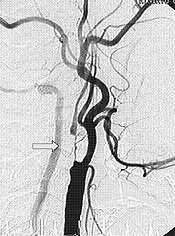

| 術前 | 術後 |

| →部分の血管のつまり(術前)をとり、血液が太く流れているのがわかる(術後)=脳血管造影 | |

アテローム硬化性脳梗塞は、首や脳内の太い動脈がひどく狭くなったりつまったりしているために、脳に送り込まれる血液量が減って脳梗塞をおこすもので す。一般に前記のような内服薬だけでは症状の進行や再発を予防できないことも多く、その場合には血液の量を増やすために外科的な治療が必要となります。

首の頸動脈が非常に狭いときは、直接血管を切開

して中のアテロームを取り出す血栓内膜剥離術を行ないます(写真)。